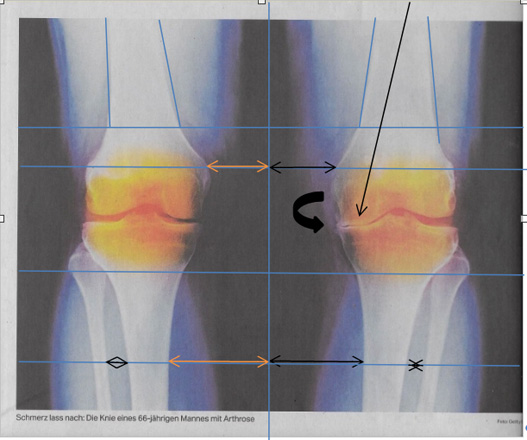

Oberkörper seitliche Ausweichhaltung führt über die Hebelwirkung zu Überbelastung der Knie-Innenseite (Folge Arthrose wird festgestellt?)

Dieses Beispiel: Abgenutzter Knorpel Ursache: Seitliche Oberkörper Ausweichhaltung |